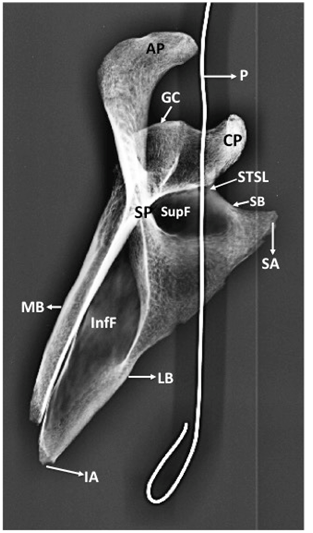

Figure 2 Posterior view of bony scapula showing.

SSF, suprascapular foramen; STSL, superior transverse scapular ligament; P, probe in SSF; CP, coracoid process; AP, acromian process; SP, spinous process; GC, glenoid cavity; SupF, supraspinous fossa; InfF, infraspinous fossa; LB, lateral border of scapula; SB, superior border of scapula; SA, superior angle of scapula

The circumference of the bony foramen was 17mm. Its superior margin was made of ossified STSL. The body of scapula constituted the inferior and medial margin. Root of coracoid process formed the lateral margin of the foramen. The maximum vertical diameter of the foramen was 7mm and the maximum transverse diameter was 4mm. The SSF was oval in shape. It was not present at the usual site but instead presented at the root of coracoid process. The margins of SSF were smooth and the foramen formed a communication between supraspinous and subscapular fossa. This was confirmed by passing a probe through the foramen. The ossified STSL, forming the superior margin of the SSF was oblique and fan shaped. It converted the suprascapular notch into a foramen. The width of STSL at the root of coracoid process was 3mm and its width at the lateral most end of superior border of scapula was 5mm. The patency of SSF was established by taking a radiological picture after putting a probe through the foramen (Figure 5) (Figure 6).